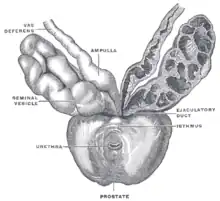

Le cancer de la prostate est un cancer fréquent touchant la prostate, une glande de l'appareil reproducteur de l'homme. Le cancer se développe à partir des tissus de la prostate quand des cellules y mutent et se multiplient de façon incontrôlée. Celles-ci peuvent ensuite s'étendre (se métastaser) en migrant de la prostate jusqu'à d'autres parties du corps, particulièrement les os et les ganglions lymphatiques du pelvis.

Le cancer entreprend la portion périphérique de la glande, au contraire de l'hypertrophie prostatique bénigne qui intéresse la zone centrale, périurétrale.

Chirurgie

Elle repose sur la prostatectomie, dite radicale ou totale. Elle consiste en l'ablation de la prostate et des vésicules séminales et peut être précédée d'un prélèvement des ganglions de drainage de la prostate. La chirurgie peut être réalisée par voie ouverte (incision chirurgicale au niveau de l'abdomen ou au niveau du périnée), par voie cœlioscopique abdominale, ou bien à l'aide de l'appareil Da Vinci ; la chirurgie est réservée aux cancers localisés à la prostate et offre de grandes chances de guérison si le cancer est effectivement localisé et peu ou moyennement agressif (agressivité estimée par le score de Gleason) ; elle peut entraîner une incontinence urinaire, le plus souvent temporaire et des troubles de l'érection. Il n'y a pas de supériorité d'une technique par rapport à une autre en ce qui concerne les résultats carcinologiques et les résultats fonctionnels urinaires et sexuels.